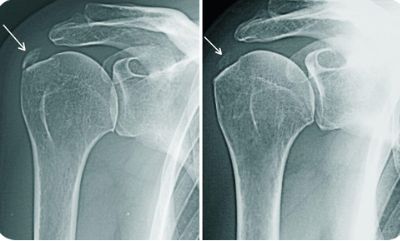

Артроз

Дегенеративная болезнь, которая характеризуется длительным течением и приводит к ограничению подвижности сустава.

Характер и локализация боли

Для артроза характерны хронические ноющие болевые ощущения в плече, которые иррадиируют в область шеи.

Усиление болевого синдрома наблюдается в ночные часы и при движениях рукой, особенно при отведении ее назад.

Симптомы артроза в начале его развития малозаметны. Обычно на начальном этапе болезни человек отмечает незначительную болезненность при движениях. По мере прогрессирования недуга боль усиливается и появляются следующие признаки:

- боль в шее отдает в руку;

- хруст в суставе при движении;

- ограничение подвижности в суставе;

- отечность в области пораженного сустава;

- покраснение кожи над больным суставом.

Диагностика и лечение

Для диагностики патологии используют:

- рентгенографию в 2-х проекциях;

- УЗИ;

- артроскопию;

- МРТ и КТ;

- сцинтиграфию;

- термографию;

- общие анализы крови и мочи;

- биохимическое исследование крови.

Лечение направлено на устранение симптомов воспаления, замедление процесса дегенерации и восстановление подвижности сустава.

Для этого используют:

- НПВП внутрь и местно;

- кортикостероиды, путем введения в полость сустава;

- обезболивающие препараты;

- хондропротекторы.

Также широко используют методы физиотерапии.

В редких случаях показана хирургическая операция по замене разрушенного болезнью сустава.